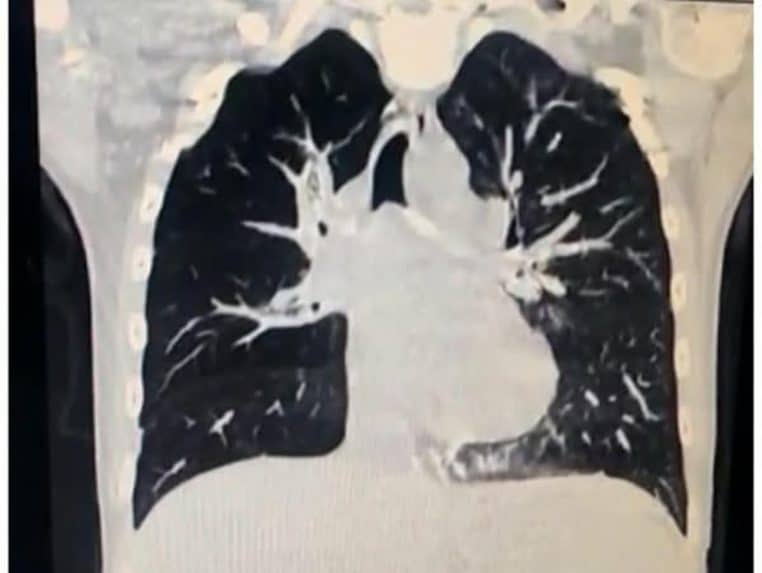

Une fois sur les lieux, les médecins ne se contentent pas d’un simple diagnostic. En effet, ils réalisent une radio des poumons, ainsi qu’une bronchoscopie pour découvrir ce qui se passe réellement. Selon leurs dires : « Après examen de ses poumons par bronchoscopie, il s’est avéré que son état était dû à un corps étranger obstruant ses voies respiratoires ».

Les images sur les radios étant assez floues, les médecins ne parviennent pas à déterminer l’objet qui se trouve dans les poumons de cette petite fille. Ils n’ont pas d’autre choix que de procéder à une intervention chirurgicale pour l’enlever. Mais l’opération n’est pas sans risques !